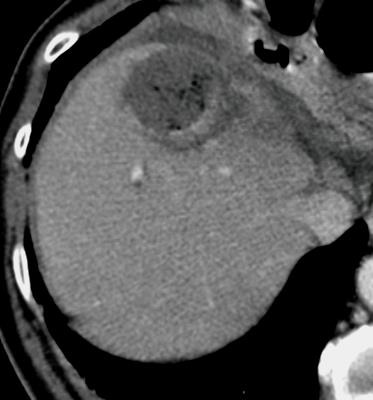

![]() ![]() ![]() ![]() 此图片的顺序待整理(查原文) ![]() ![]() ![]() ![]() Histologically-Proven Efficacy of Bland Embolization in a Patient with Net Liver Metastasis TAE 适应症之三:GIST